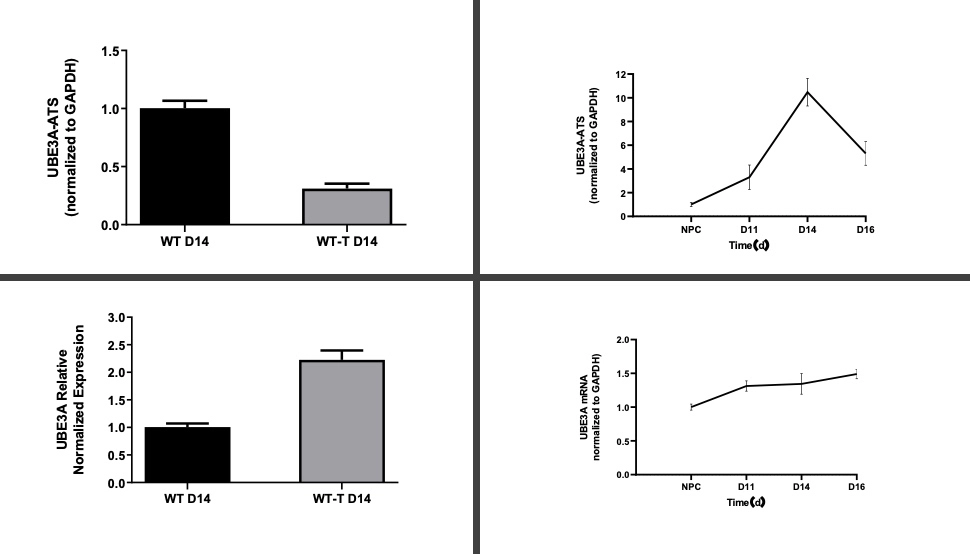

研究目标:利用 iPSC 衍生的皮层神经元评估靶向 UBE3A 的 ASO 的疗效。

ASO 治疗: 在第 14 天对神经元进行给药,并持续监测 9 天

基因表达分析: 通过 qPCR 检测到 UBE3A 表达上调,同时 UBE3A-ATS 表达下调

关键结果

结果证明了 ASO 在调节神经元模型中的靶基因方面的有效性,突显了其在神经治疗应用方面的潜力。